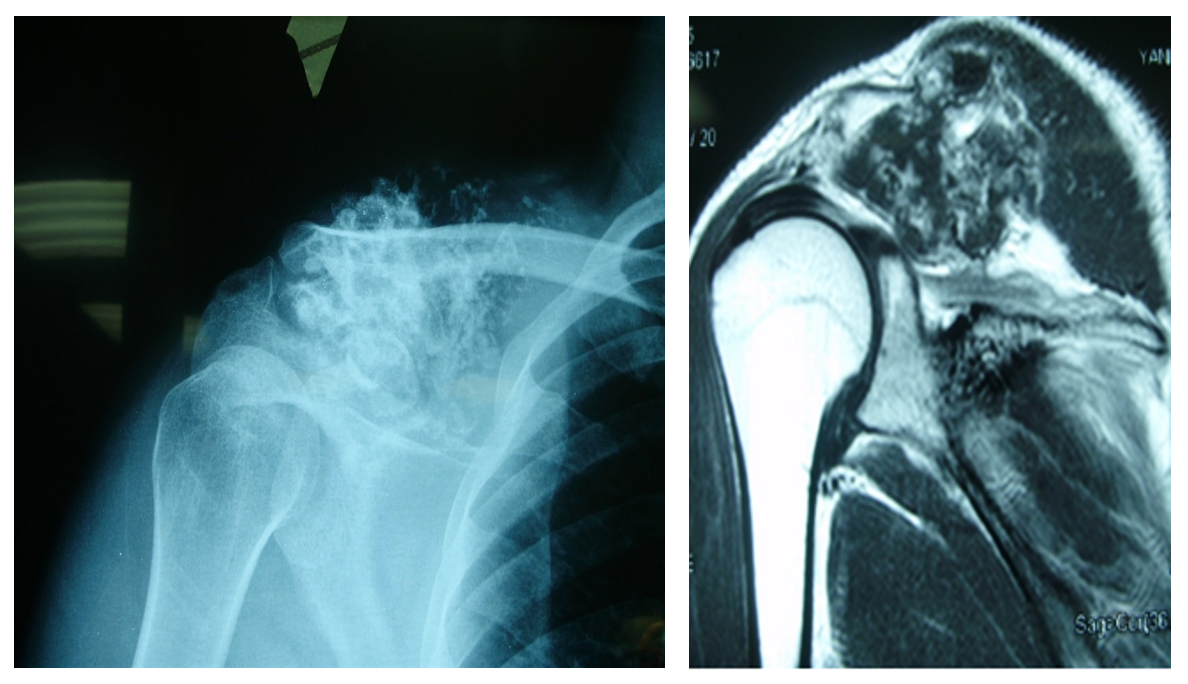

Vaka 04: Köprücük Kemiği (Klavikula) Yerleşimli Kondrosarkom

Genç erkek hasta, köprücük kemiği bölgesinde şişlik, ağrı ve hareket kısıtlılığı şikayetleri ile başvurmuş; biyopsi sonucunda kondrosarkom tanısı doğrulanmıştır. Yapılan değerlendirmelerde cerrahi için uygun bulunmuştur.

Ameliyat Öncesi: Röntgen ve tomografide klavikula üzerinde düzensiz sınırlı kıkırdak dokusu içeren tümör dokusu görülmekte.

Ameliyat Sonrası: Röntgende parsiyel klavikulektomi sonrası oluşan boşluk görülmekte.